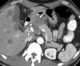

Extragastric malignancy